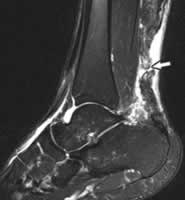

患者病史和年齡可提示診斷。臨床症狀有:(1)跟腱可見裂隙;(2)足抗跖屈阻力減弱;(3)再次行足抗跖屈阻力檢查時,在斷裂跟腱處側方擠壓缺乏“堅硬”感。X片上軟組織影、超聲以及MRI檢查均顯示跟腱缺乏連續性。